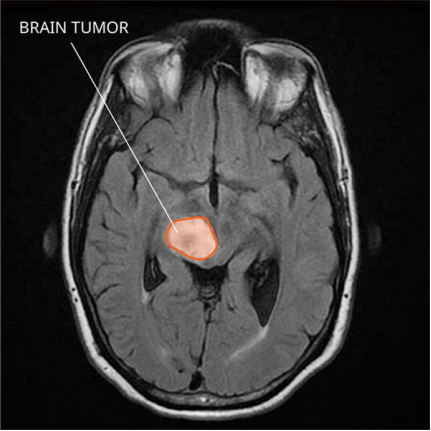

胶质瘤常常难以治疗不完全,复发成为常事。每两个脑肿瘤病人中,就有一个是胶质瘤患者。胶质瘤不仅是颅内较常见的肿瘤,而且大多是高程度恶性肿瘤。手术切除目前是胶质瘤的合适治疗方法,但是一般难以切除干净,常常会复发。即使医生在术中将肉眼可见的肿瘤切除掉了,就算切干净了。 但是,由于胶质瘤浸润性生长的特点,有些肿瘤细胞与正常脑组织混合在一起,看起来也象正常组织,就会骗过医生的眼睛。

除了胶质瘤浸润性生长的特点,另外,由于神经胶质细胞广泛分布于颅内的各个部位,而起源于胶质细胞的胶质瘤也可长在颅内各种部位。所以对于脑干、丘脑、桥脑等高难度位置的胶质瘤,由于手术难度过大,医生只能在避免损伤脑组织的同时,尽量的去切除脑胶质瘤,导致切除率并不高,所以常常复发。对于放射或者化疗治疗的脑胶质瘤患者,一般只能起到控制作用,一段时间再次复发也是正常的。所以,对于治疗不完全的胶质瘤,大多数都会复发的。那么,胶质瘤复发能活多久呢?